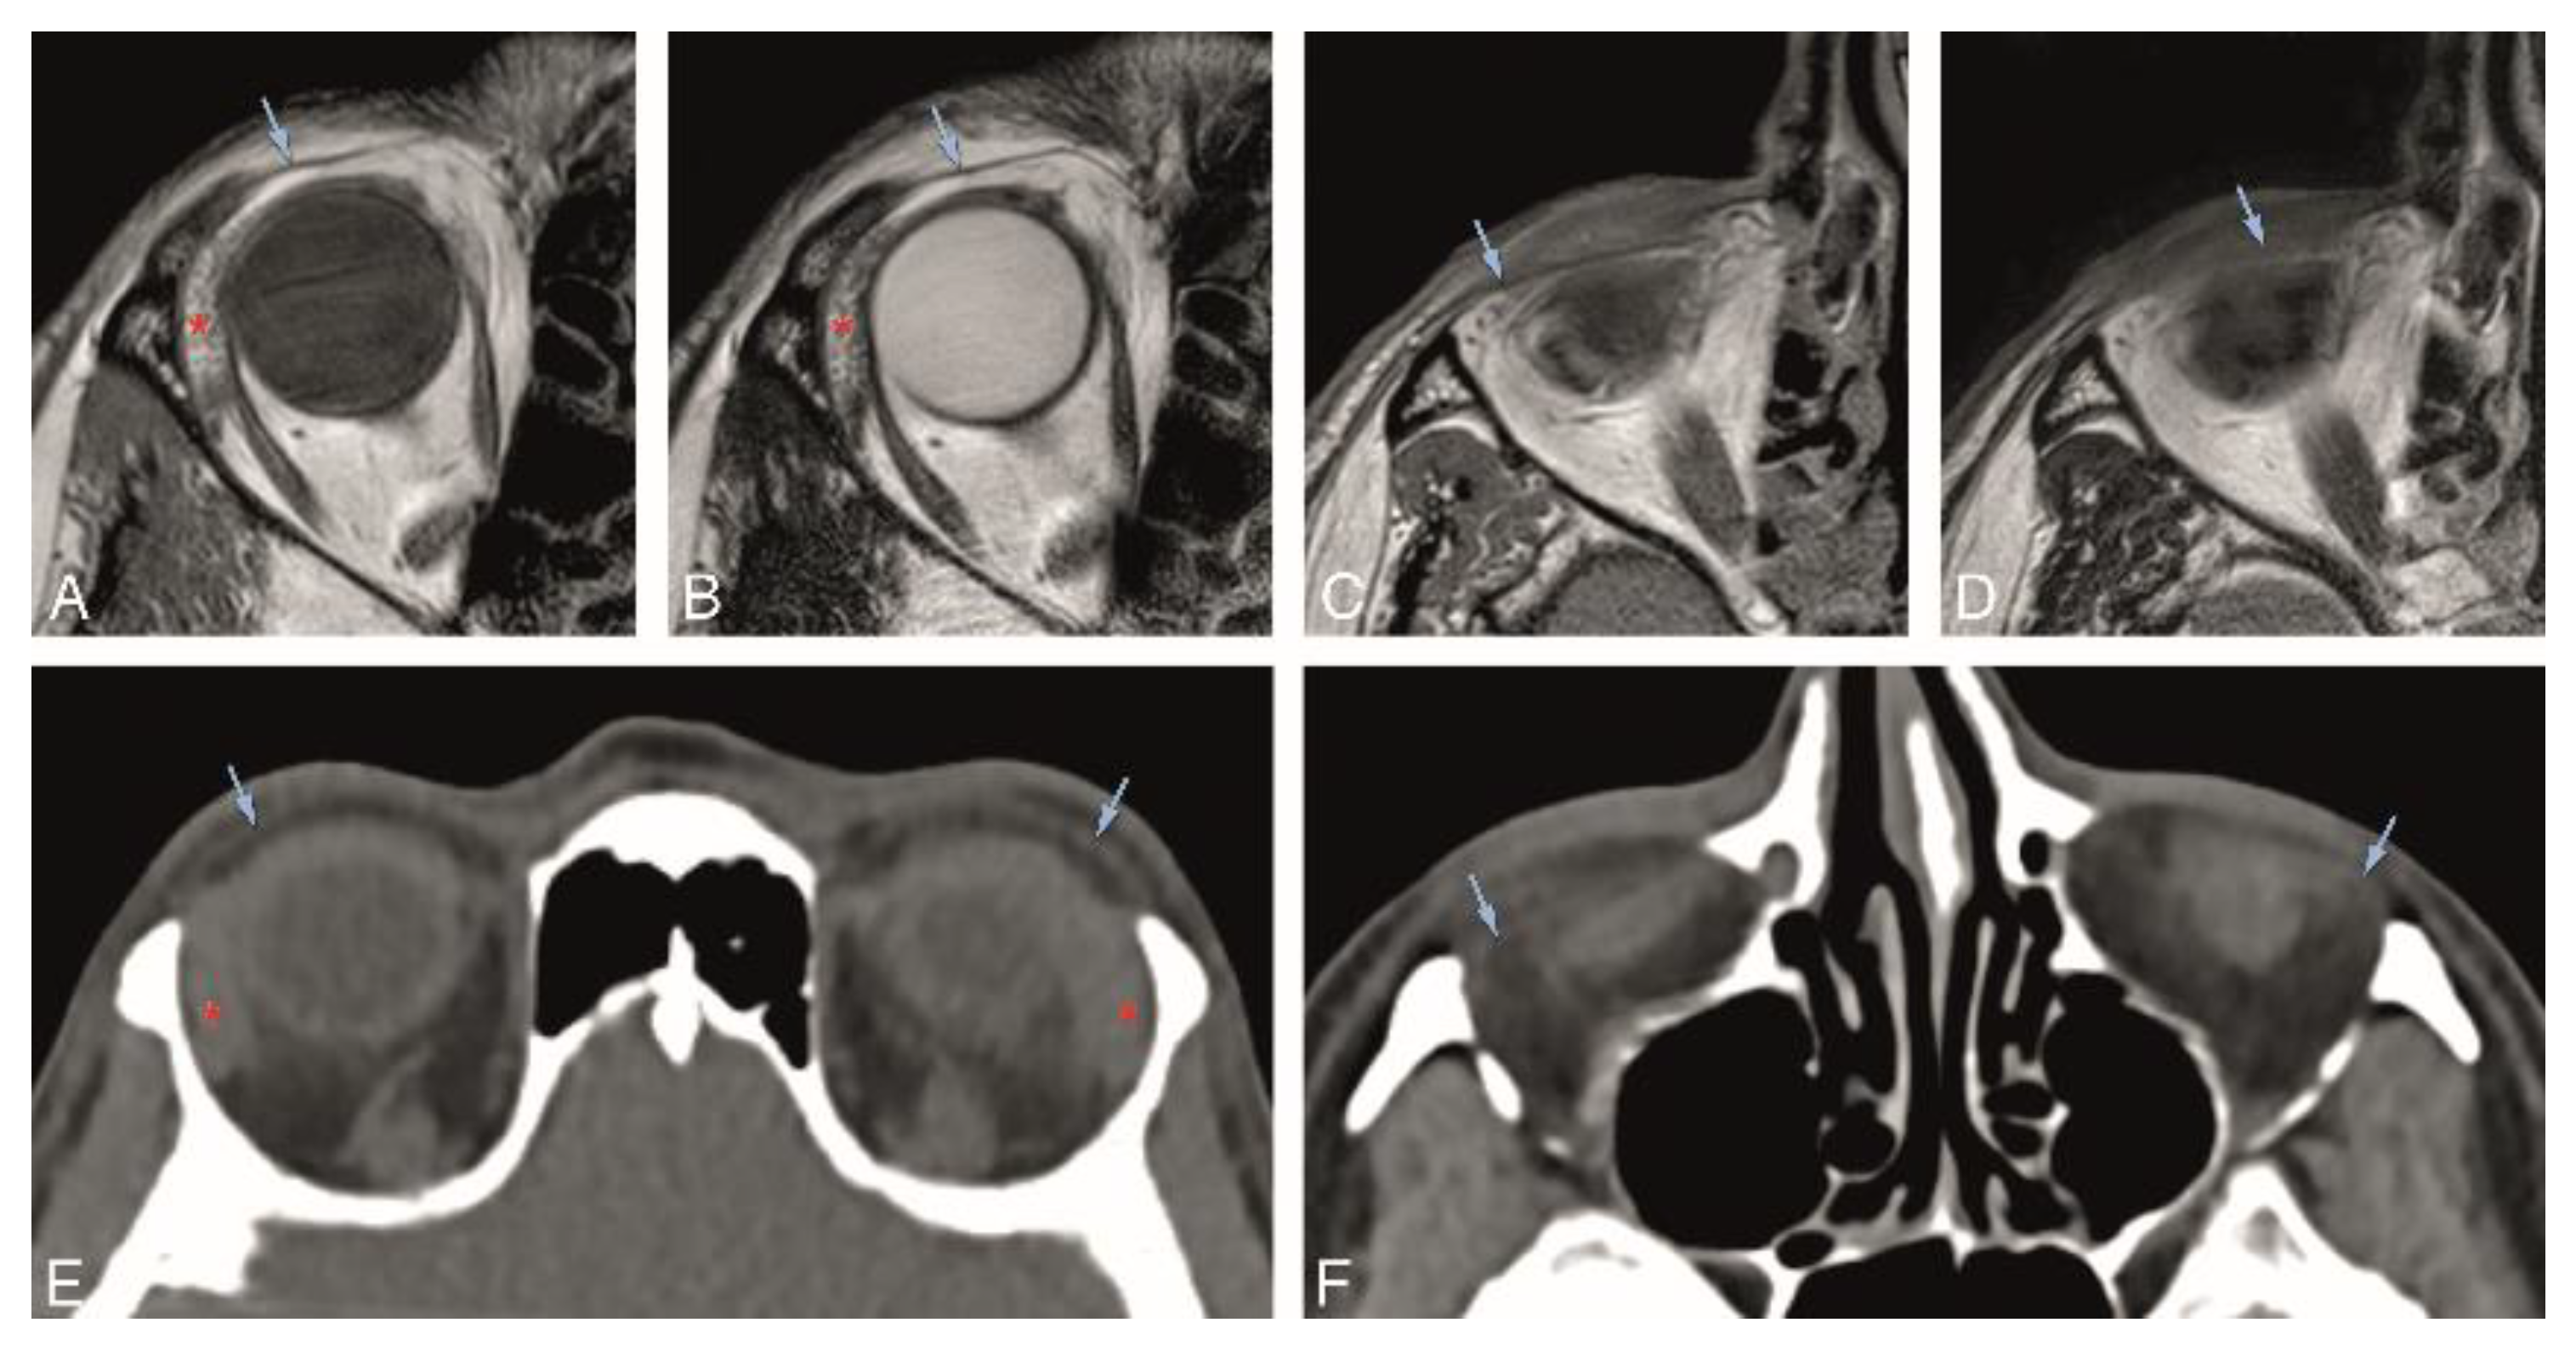

Figure 4. A, B, and E: Normal superior orbital septum (blue arrow) on the axial plane on MR T1-WI (A), T2-WI (B), and on CT (E). C, D, and F: Normal inferior orbital septum (blue arrow) on the axial plane on MR T1-WI (C), T2-WI (D), and on CT (F). Blue arrow: orbital septum; red asterisk: lacrimal gland.

In Group 1, the visibility of the superior and inferior tarsal plates and orbital septa was scored on MRI (Table 1). Both the superior and inferior tarsal plates were identifiable in 94% of the subjects, being the superior tarsal plate well-defined in 78% and the inferior tarsal plate well-defined in 67% of the subjects. The superior tarsus was easier to identify on the axial plane. The inferior tarsus was equally well visible on the axial and sagittal planes (Figure 2A,E,F, and Figure 3A–D). The superior septum was always visible, being well-defined in 92% of the subjects. The inferior septum was visible in 91% of the subjects, but it was well-defined in only 36% of the subjects. The superior and inferior septa were easier to identify on the sagittal plane (Figure 2A,B,E,F, and Figure 4A–D). Orbital septa and tarsal plates were more difficult to identify when the slices were not acquired perpendicular to the main axis of the eyelid, and when movement artifacts were present. In Group 2, and similarly to Group 1, the superior and inferior tarsal plates and orbital septa were scored (Table 2). The superior tarsus was always visible, being well-defined in 63% of the subjects. The inferior tarsus was visible in 84% of the subjects and was well-defined in 53% of the subjects. Both the superior and inferior tarsal plates were better depicted on the axial plane than on the sagittal plane (Figure 2G and Figure 3E,F). The superior septum was visible in 89% of the subjects and well-defined in 47% of the subjects. The inferior septum was visible in 68% of the subjects, but well-defined only in 11% of the subjects. The superior and inferior septa were easier to identify on the axial plane (Figure 2C,G and Figure 4E,F) than on the sagittal plane.